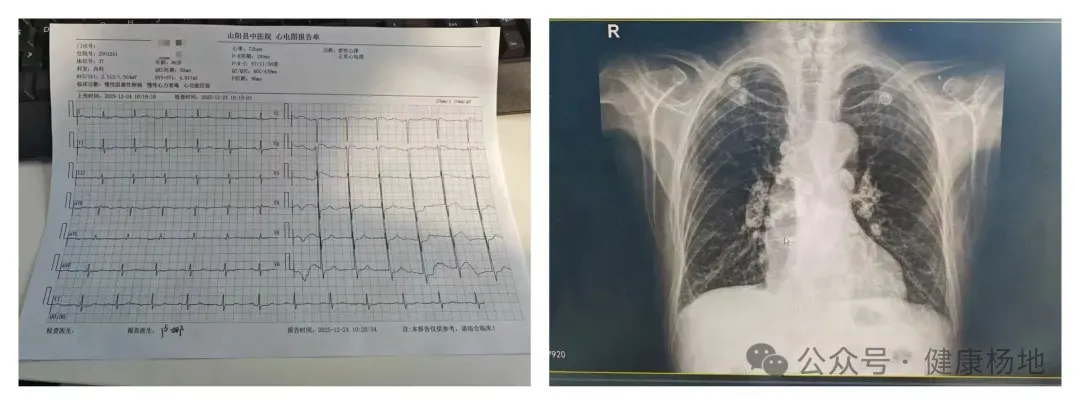

12月20日,患者刘某某由家属轮椅推入送至山阳县杨地镇卫生院。入院时,患者神志虽清,但精神状态极差。接诊的王伟医生立即为其完善相关检查:胸片提示两肺间质增生并两下肺炎症,两肺门多发淋巴结钙化;心电图显示窦性心律、房性早搏、ST-T改变;B型脑钠肽数值高达1667.52pg/ml,远超正常范围,提示心功能严重受损。山阳县杨地镇卫生院医护团队第一时间启动诊疗预案,为患者制定针对性治疗方案,密切监测病情变化。

12月22日11时30分,护士在病房巡查时敏锐发现,患者呼吸频率、心率异常加快。值班医护迅速为其急查心电图,结果提示窦性心动过速、室性早搏、房性早搏。医护团队当即开启心电监护,紧盯患者生命体征。十余分钟后,患者突发烦躁不安,自诉胸闷不适,伴随大汗淋漓,血压飙升至195/136mmHg,体温38℃,心电监护显示心率130次/分,血氧饱和度仅89%,呼吸频率达35次/分。听诊可见心音亢进,双肺满布湿罗音——典型的急性左心衰竭症状!